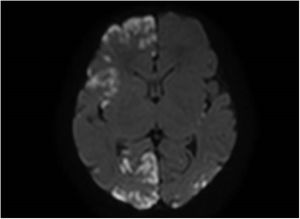

A female full-term neonate developed clonic seizures in the left side of the body in the first day of life accompanied by eye deviation. The seizures were refractory to first-line anticonvulsant therapy and resolved with phenytoin. The brain MRI revealed diffuse hyperintense cortical lesions with an extensive, bilateral and patchy distribution at the periventricular and subcortical levels (Fig. 1). The EEG, infectious and metabolic disease tests and ophthalmological evaluation were normal.